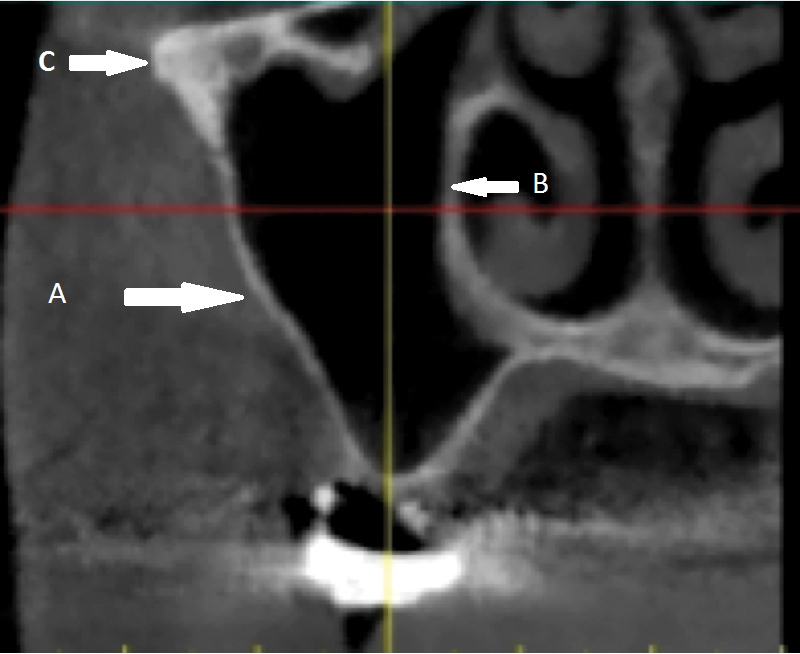

Fig 14. Maxillary sinus: cross-sectional view. A: Buccal wall. B: Medial wall. C: Zygomatic arch.

Figure 14